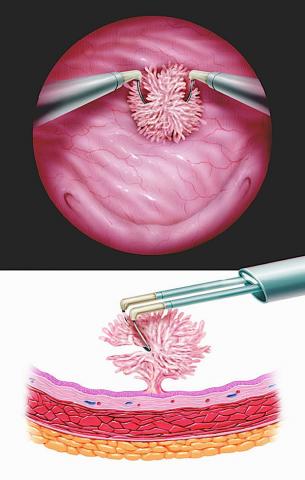

Mesane TUR Ameliyatı (Transüretral Rezeksiyon)

Mesane Kanseri Tedavisi-TUR-M

Mesane TUR ameliyatı, erken evre mesane tümörlerinin endoskopik yöntemle çıkarılmasıdır. İşlem idrar kanalından girilerek yapıldığı için vücutta kesi oluşturulmaz. Tümörün tamamı kazınarak alınır ve patoloji sonucuna göre BCG veya kemoterapi gibi ek tedavilere ihtiyaç olup olmadığı değerlendirilir. Bu yöntem, hem tanı hem de tedavinin ilk basamağını oluşturur. TUR-Mesane ameliyatı için daha detaylı bilgi için TUR M Ameliyatı sayfasını ziyaret edin.

➡ TUR-M (Transüretral Rezeksiyon)

İdrar kanalından girilerek tümör kazınır.

Kesi yapılmaz.

Hem tanı hem tedavinin ilk basamağıdır.

Gerekirse re-TUR-M yapılır (özellikle T1 veya belirsiz yerlerde).